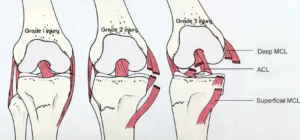

What is a Ligament Tear? A ligament tear happens when the tough bands that connect your bones get stretched or torn. These bands, called ligaments,

Introduction to Knee Ligament Injury Knee ligament injuries are common, especially among active people. Minimally invasive knee ligament surgery is now a popular treatment. Ligaments

The medial collateral ligament (MCL) is crucial for stabilizing the knee. Together with other ligaments, it ensures the knee moves correctly and supports weight. When